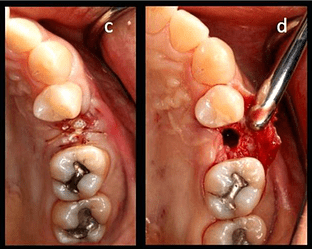

Case photos provided by: Clinical evaluation of 3D printed nano-porous hydroxyapatite bone graft for alveolar ridge preservation: A randomized controlled trial](Clinical evaluation of 3D printed nano-porous hydroxyapatite bone graft for alveolar ridge preservation: A randomized controlled trial - PMC)

Process diagram of clinical procedure; a) Cracked tooth #25; b) #25 Atraumatic extraction; c) Placement of HA hydroxyapatite granules in alveolar socket after atraumatic extraction, with closing of the socket by Cytoplast™ and suturing; d, e) After four months, harvesting of the grafted area with a trephine bur in formalin solution.